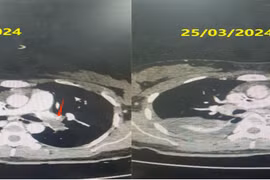

Thuyên tắc phổi cấp do huyết khối là một trong những nguyên nhân hàng đầu gây tử vong ở phụ nữ mang thai ngay cả tại những nước phát triển. Bệnh viện Chợ Rẫy đã phải phối hợp nhiều chuyên khoa để cứu sống mẹ con sản phụ.

Thuyên tắc phổi cấp là hội chứng tim mạch cấp tính thường gặp, đứng thứ 3 trên toàn thế giới sau nhồi máu cơ tim và đột quỵ não. Bệnh không có triệu chứng điển hình cần được phát hiện sớm.